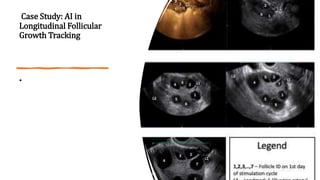

Case Study: AI in

Longitudinal Follicular

Growth Tracking

•

Summary: Tracking follicles between days 1-4 is sufficient to

predict their size at

the end of cycle

Average Rate of Growth

(in mm/day)

Between days Inference

>1 1-4

Follicle will grow to

>10mm at end of cycle

0.6 – 1

(increasing)

1-4

Follicle will be between

4mm-10mm at the end

of cycle

0.6 – 0.1

(decreasing)

Follicle will have size

<4mm at end of cycle